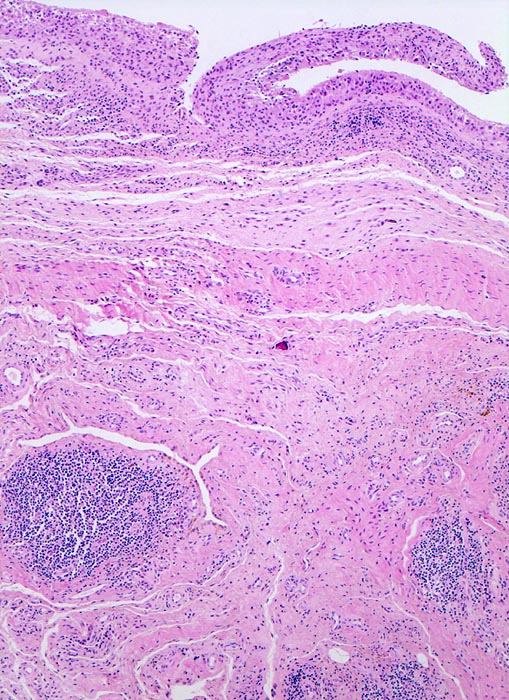

Typische histologische Veränderungen sind eine synoviale Zottenhyperplasie, Verbreiterung der Deckzellschicht unter Einschluss mehrkerniger Riesenzellen, Fibrinexsudate und synoviale Ulzerationen, Infiltrate von Lymphozyten teils in Form von Lymphfollikeln, Plasmazellen, neutrophilen Granulozyten, Makrophagen und Siderophagen, sowie Einschlüsse von Knorpel- und Knochenfragmenten (Detritussynovialitis). Die histologischen Befunde der Synovialis korrelieren oft nicht mit den klinischen Angaben. Trotz fortgeschrittener Gelenkdestruktion mit ausgeprägter klinischer Symptomatik können Synovialektomiepräparate nur sehr geringe pathologische Veränderungen zeigen. Oft ist auch nicht mehr zu eruieren, welche Läsionen Folge der Grundkrankheit und welche Folge diverser intraartikulärer Therapien oder begleitender Superinfektionen sind.

• Synovialis mit verplumpten Zotten.

• Stark proliferierte mehrreihige synoviale Deckzellschicht.

• Herdförmig Fibrinauflagerungen durchsetzt von neutrophilen Granulozyten.

• Hyperzelluläres Stroma mit lymphoplasmazellulärem Entzündungsinfiltrat mit Ausbildung von Lymphfollikeln.